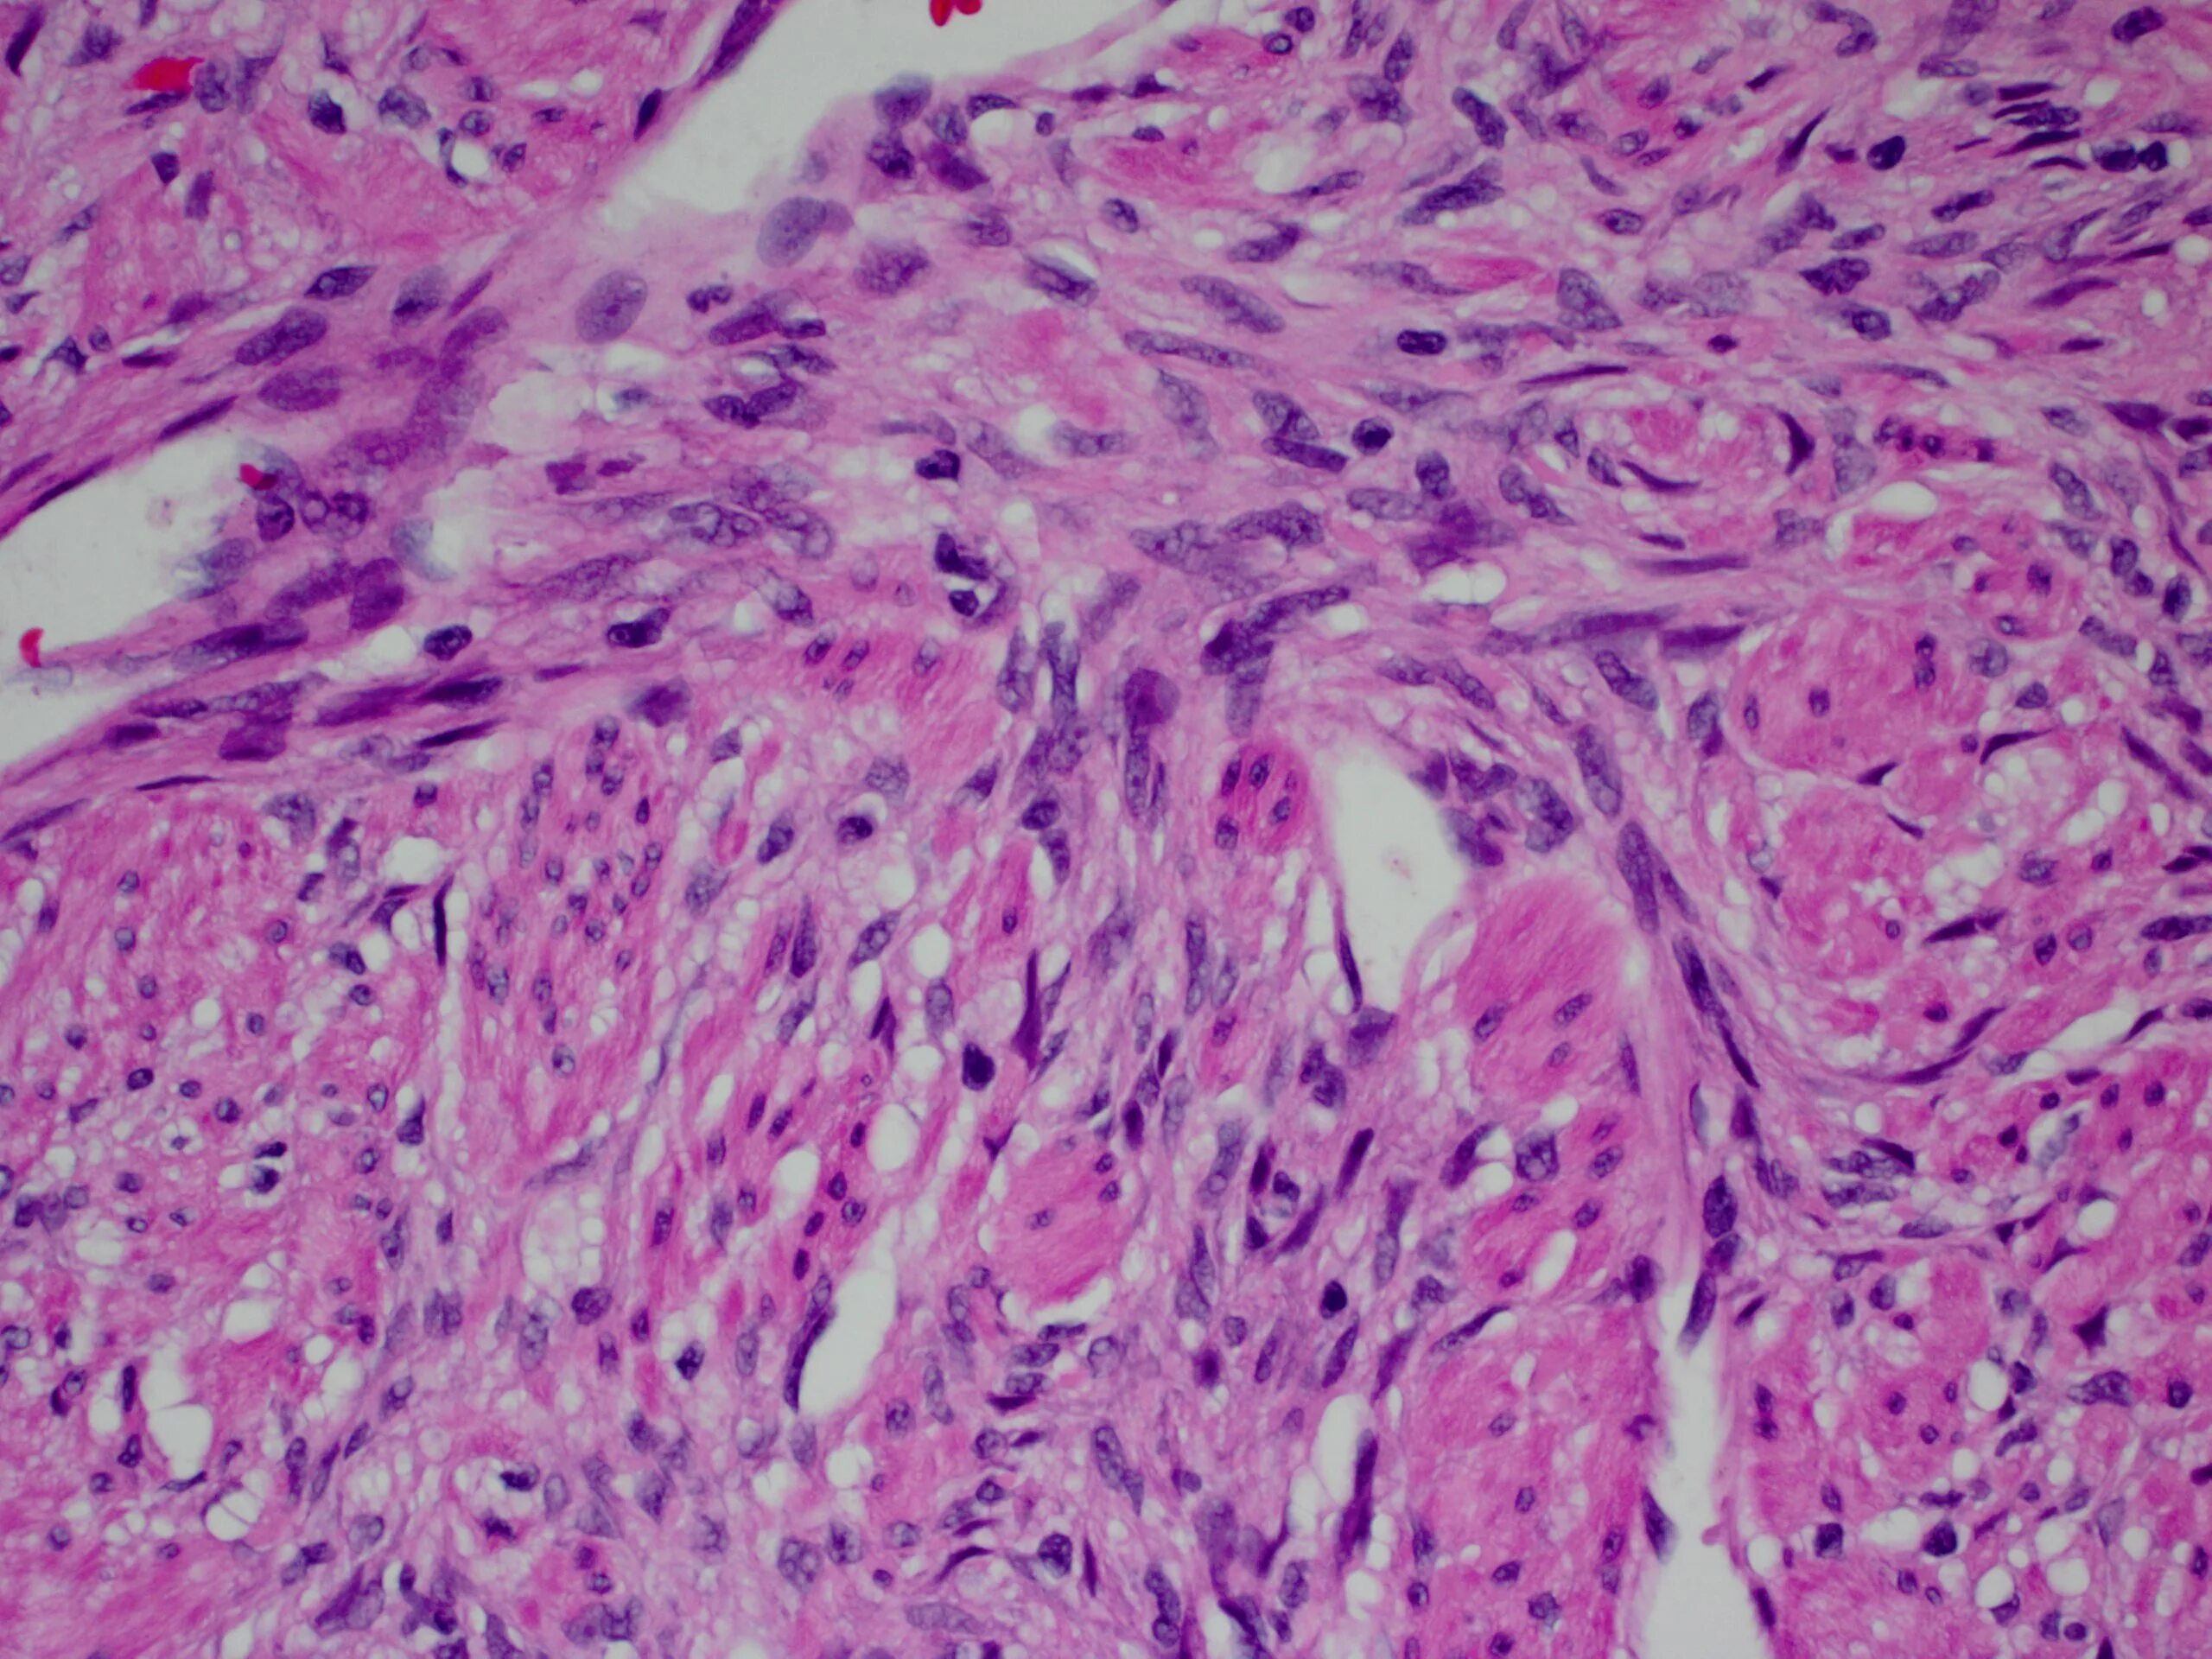

Ошибочная гистология